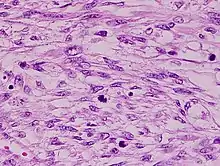

The tumors are usually hemorrhagic and soft and microscopically marked by pleomorphism, abundant (15–30 per 10 high-power fields) abnormal mitotic figures, and coagulative tumor cell necrosis. The differential diagnosis, which includes spindle cell carcinoma, spindle cell melanoma, fibrosarcoma, malignant peripheral nerve sheath tumor and even biphenotypic sinonasal sarcoma, is wide.